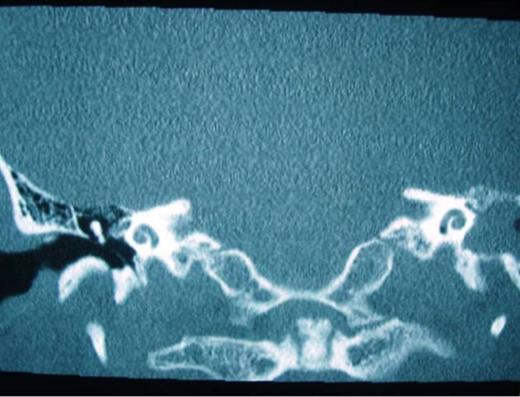

When surgery was attempted, cochleostomy revealed complete obliteration of the scala tympani. Efforts to insert the electrode through the scala vestibuli were also unsuccessful. The procedure was abandoned and a subsequent high resolution CT scan showed complete ossification of the left cochlea and but a patent cochlea on the right (Fig. 3 and 4). Twenty days following the initial attempt, a right cochlear implantation was successfully performed. Following mapping, programming, and aural rehabilitation, the patient was able to understand speech and use the telephone.